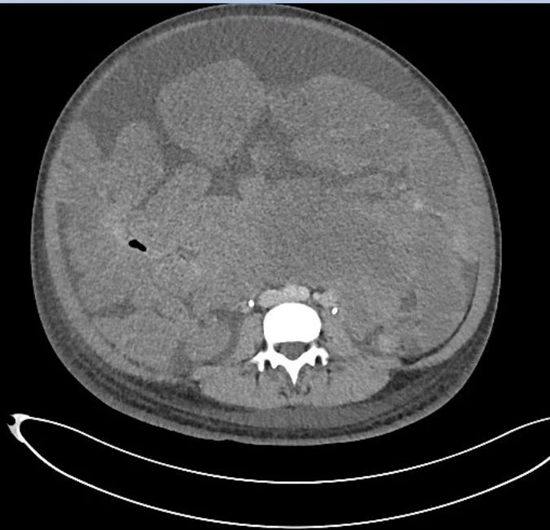

•     程小曼的腹部CT片,浅灰色的不规则团块均为肿瘤。受访者供图

他把那里比作“布满鹅卵石的海滩”。原本应该是肠管的位置看不到一段肠子,只有挤作一团的肿瘤。腹腔内唯一可见的正常器官是胃的下部。血管被挤到一旁,由于供养着密密麻麻、黄豆到蚕豆大小的肿瘤,直径变成正常血管的3倍。